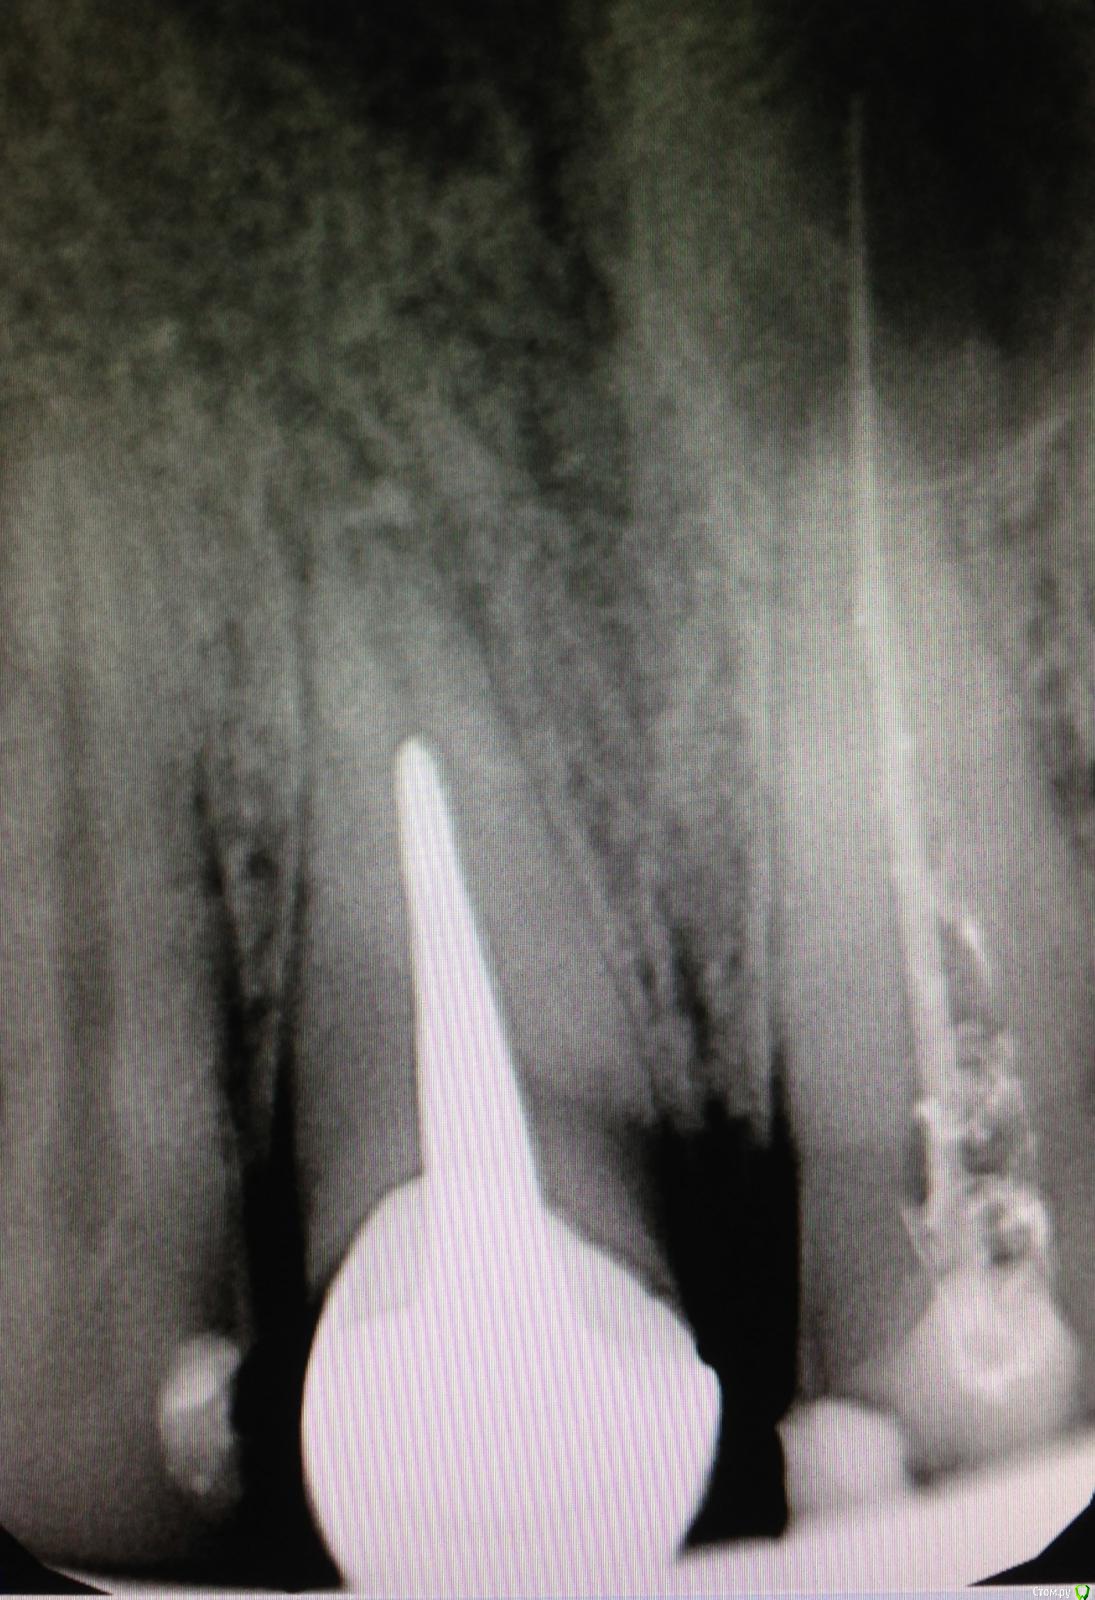

SSTi Опубликовано 27 декабря, 2014 Автор Поделиться Опубликовано 27 декабря, 2014 Вот так бывает. Красота. 21 оставил пока кальций. 11 запаковал. 2 Ссылка на комментарий